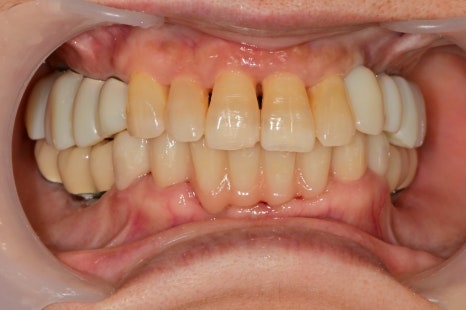

임플란트가 안정화가 되기를 기다리며

임시틀니를 끼며

무너진 교합을 회복하고

남아 있는 자연치아의 회복을 시킨 후

턱관절의 안정을 시키기 위해 임시치아를 사용하는 기간도 갖습니다.

위 앞니를 보시면 무너진 교합을 회복시켜주고

자연치아가 회복할 시간을 주니

저절로 앞니도 이쁘게 제자리를 찾았습니다.

꽤나 긴 시간 동안 임시틀니를 사용하셨는데

이제 정상적인 저작을 하실 수 있다고 하셔서

너무 보람찬 순간이었습니다.^^